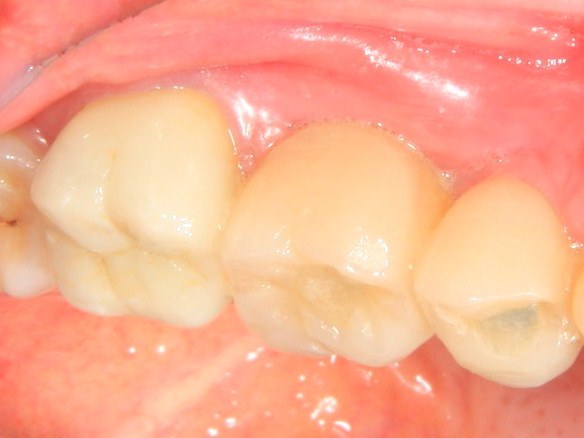

Немедленная имплантация — оптимальное решение в любой клинической ситуации